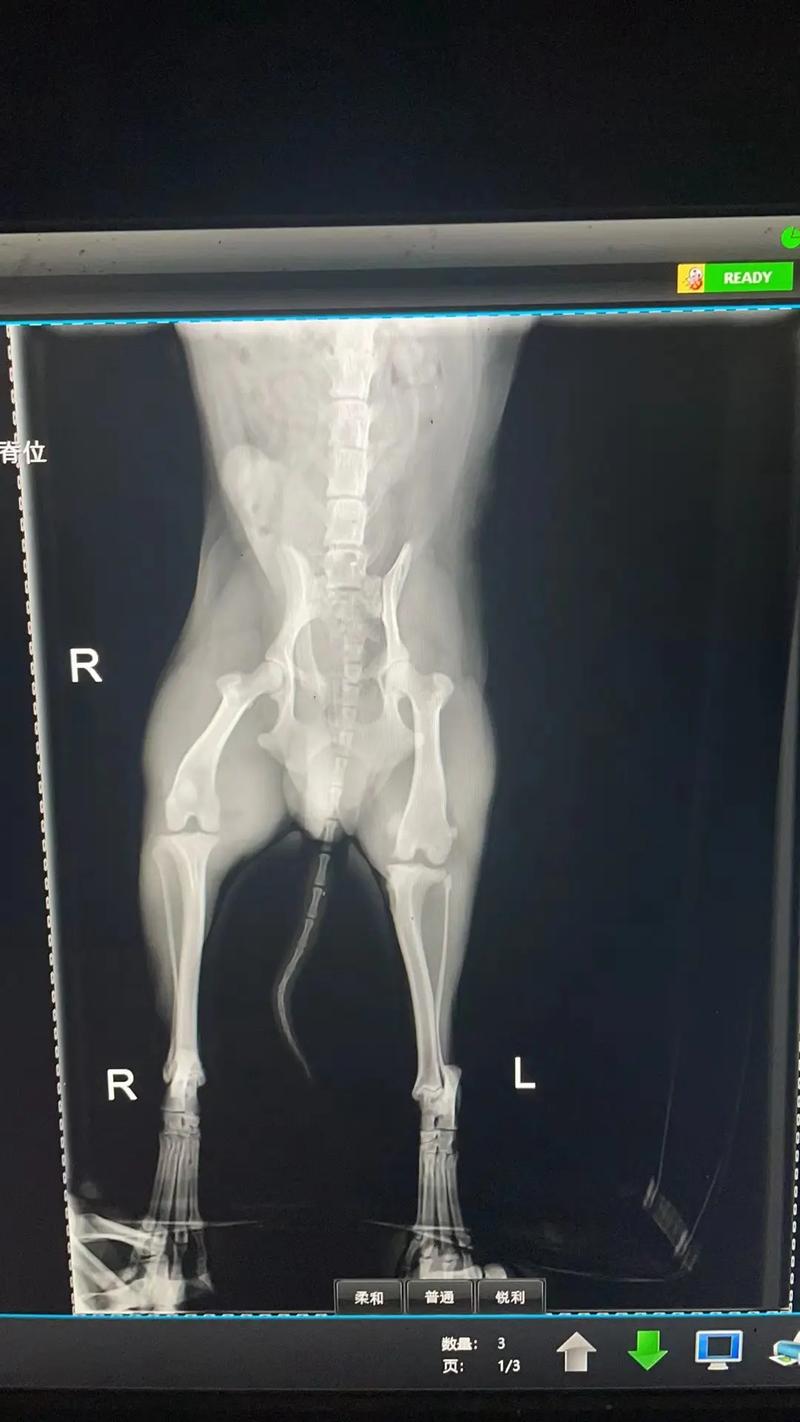

狗狗X光片的费用通常在80-120元/部位/张,为了确诊,同一部位可能需要拍摄两次,总计160-240元。而牙齿CT的费用大约在40-60元。 为了避免交叉感染,人去的医院通常不允许狗狗进入。正规宠物医院拍片的费用大约在60至80元。 狗狗做B超的费用通常比拍片便宜,一般在几十元人民币。

狗狗拍一个x光片多少钱一般宠物医院的标价在80-120元/体位/张,比如胸部,腹部,腿部这样区分,通常为了确诊,同样的部位会拍两个体位,也就是160-240元。人去的当然不能让狗进啦,避免交叉感染嘛。正规的宠物都可拍片,拍片的费用在60至80元。那么狗狗做B超一般多少钱。

〖伍〗、一般宠物医院的标价在80-120元/体位/张,比如胸部,腹部,腿部这样区分,通常为了确诊,同样的部位会拍两个体位,也就是160-240元。

〖叁〗、一般宠物医院的标价在80-120元/体位/张,比如胸部,腹部,腿部这样区分,通常为了确诊,同样的部位会拍两个体位,也就是160-240元。

一般宠物医院的标价在80-120元/体位/张,比如胸部,腹部,腿部这样区分,通常为了确诊,同样的部位会拍两个体位,也就是160-240元。